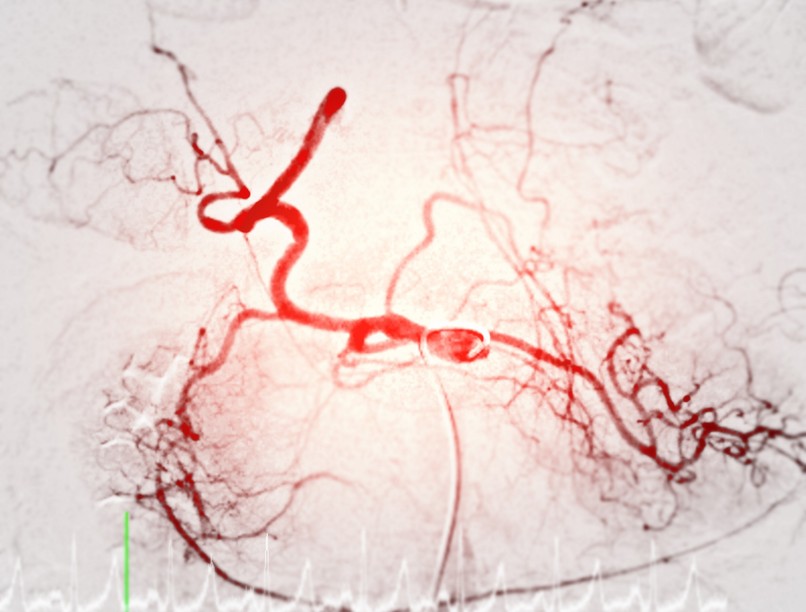

Az arteriográfia egy speciális orvosi képalkotó vizsgálat, amelyet az artériák állapotának felmérésére használnak. Ez a módszer kontrasztanyagos röntgenvizsgálaton alapul, és lehetővé teszi az érrendszer pontos megjelenítését. Az arteriográfiát gyakran alkalmazzák szív- és érrendszeri betegségek diagnosztizálására, érszűkületek vagy elzáródások kimutatására, valamint a stroke és a szívinfarktus kockázatának felmérésére.

• Stroke kockázatának felmérése: az agyi erek állapotának vizsgálata.